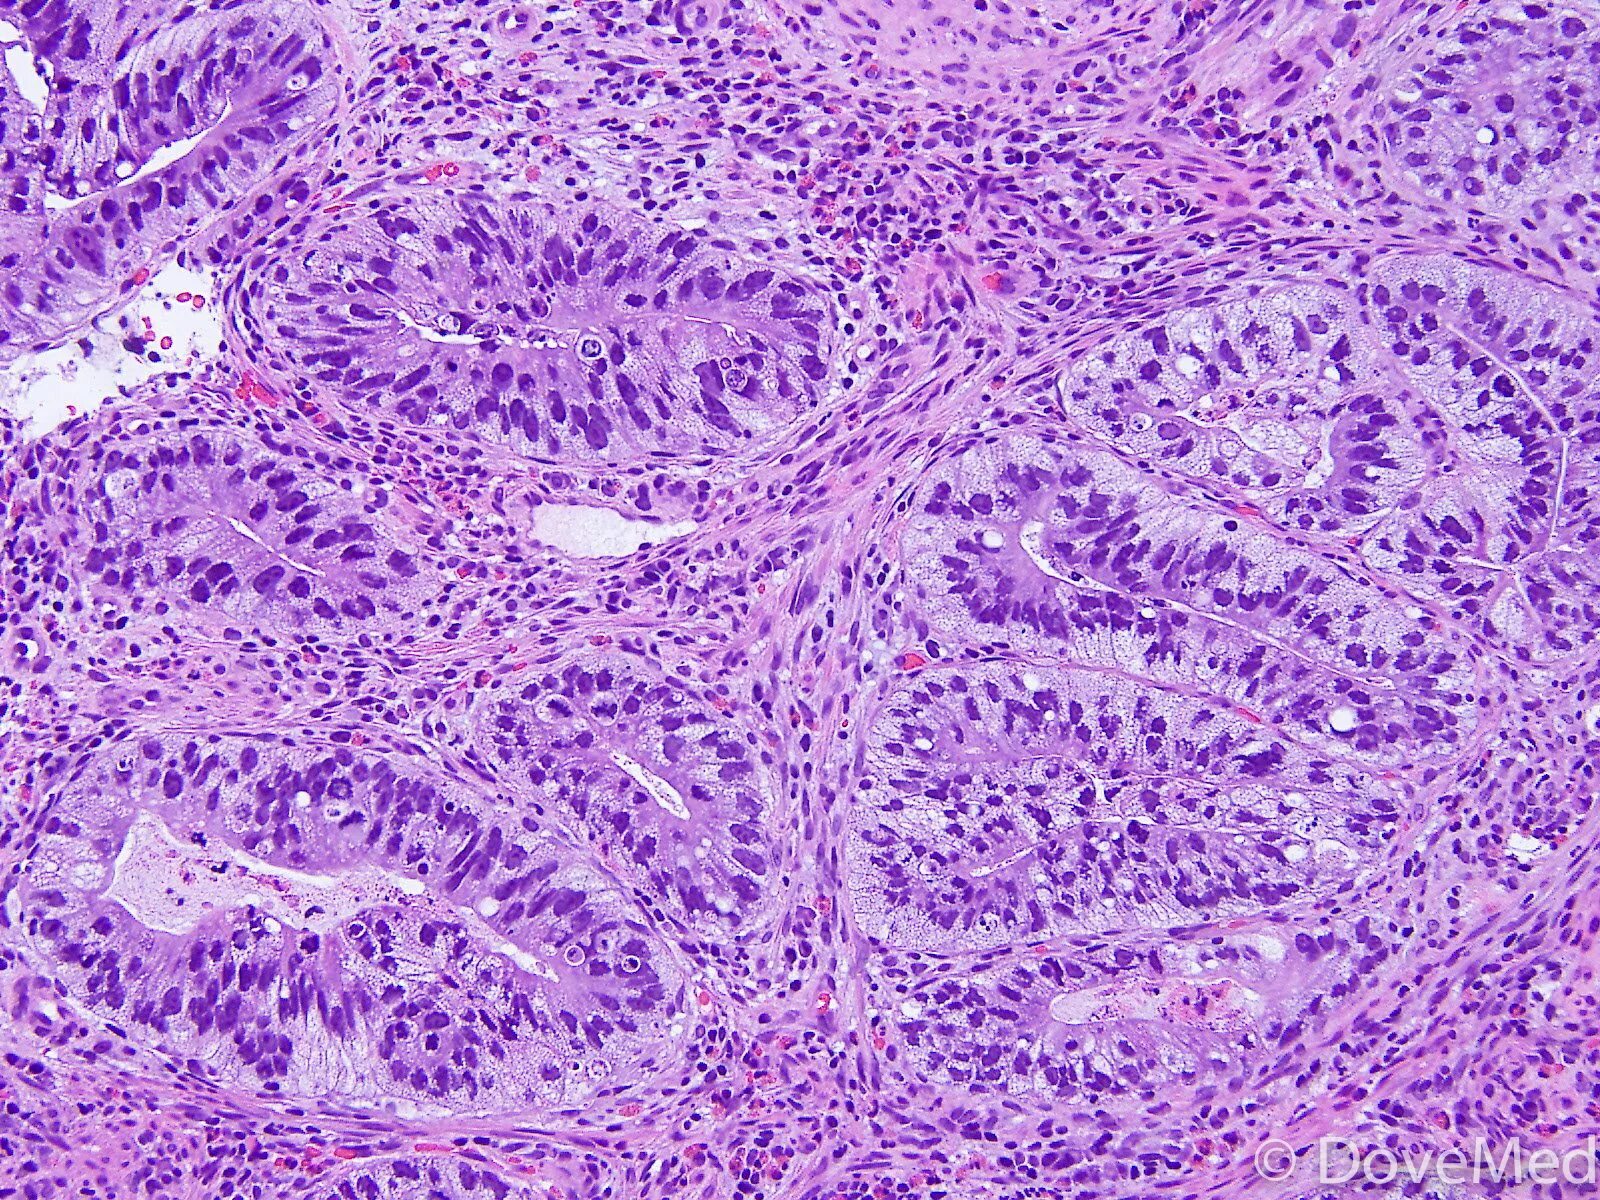

Гистологически аденокарцинома